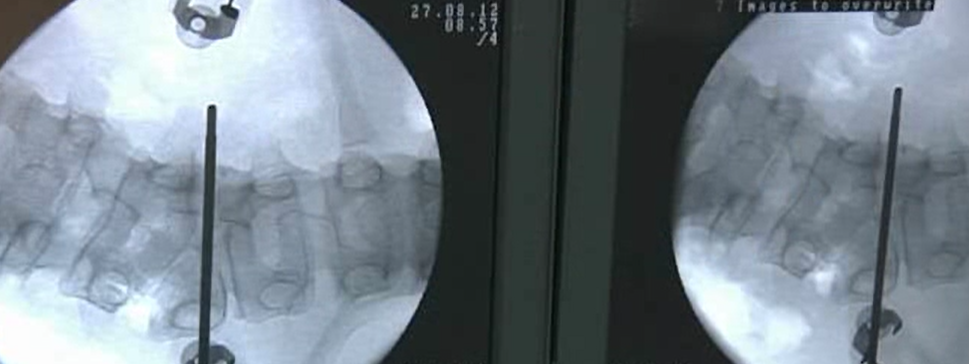

This video demonstrates the posterior approach to the vertebral body, O-arm based pedicle screw insertion, asymmetric ...